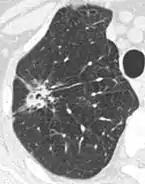

Thin slice and maximal intensity projection of a lung nodule, the latter better visualizing vascular convergence.[9]

• Vascular convergence is where vessels converge to a nodule without adjoining or contacting the edge of the nodule, and is mainly seen in peripheral subsolid lung cancers.[9] It reflects angiogenesis.[9]